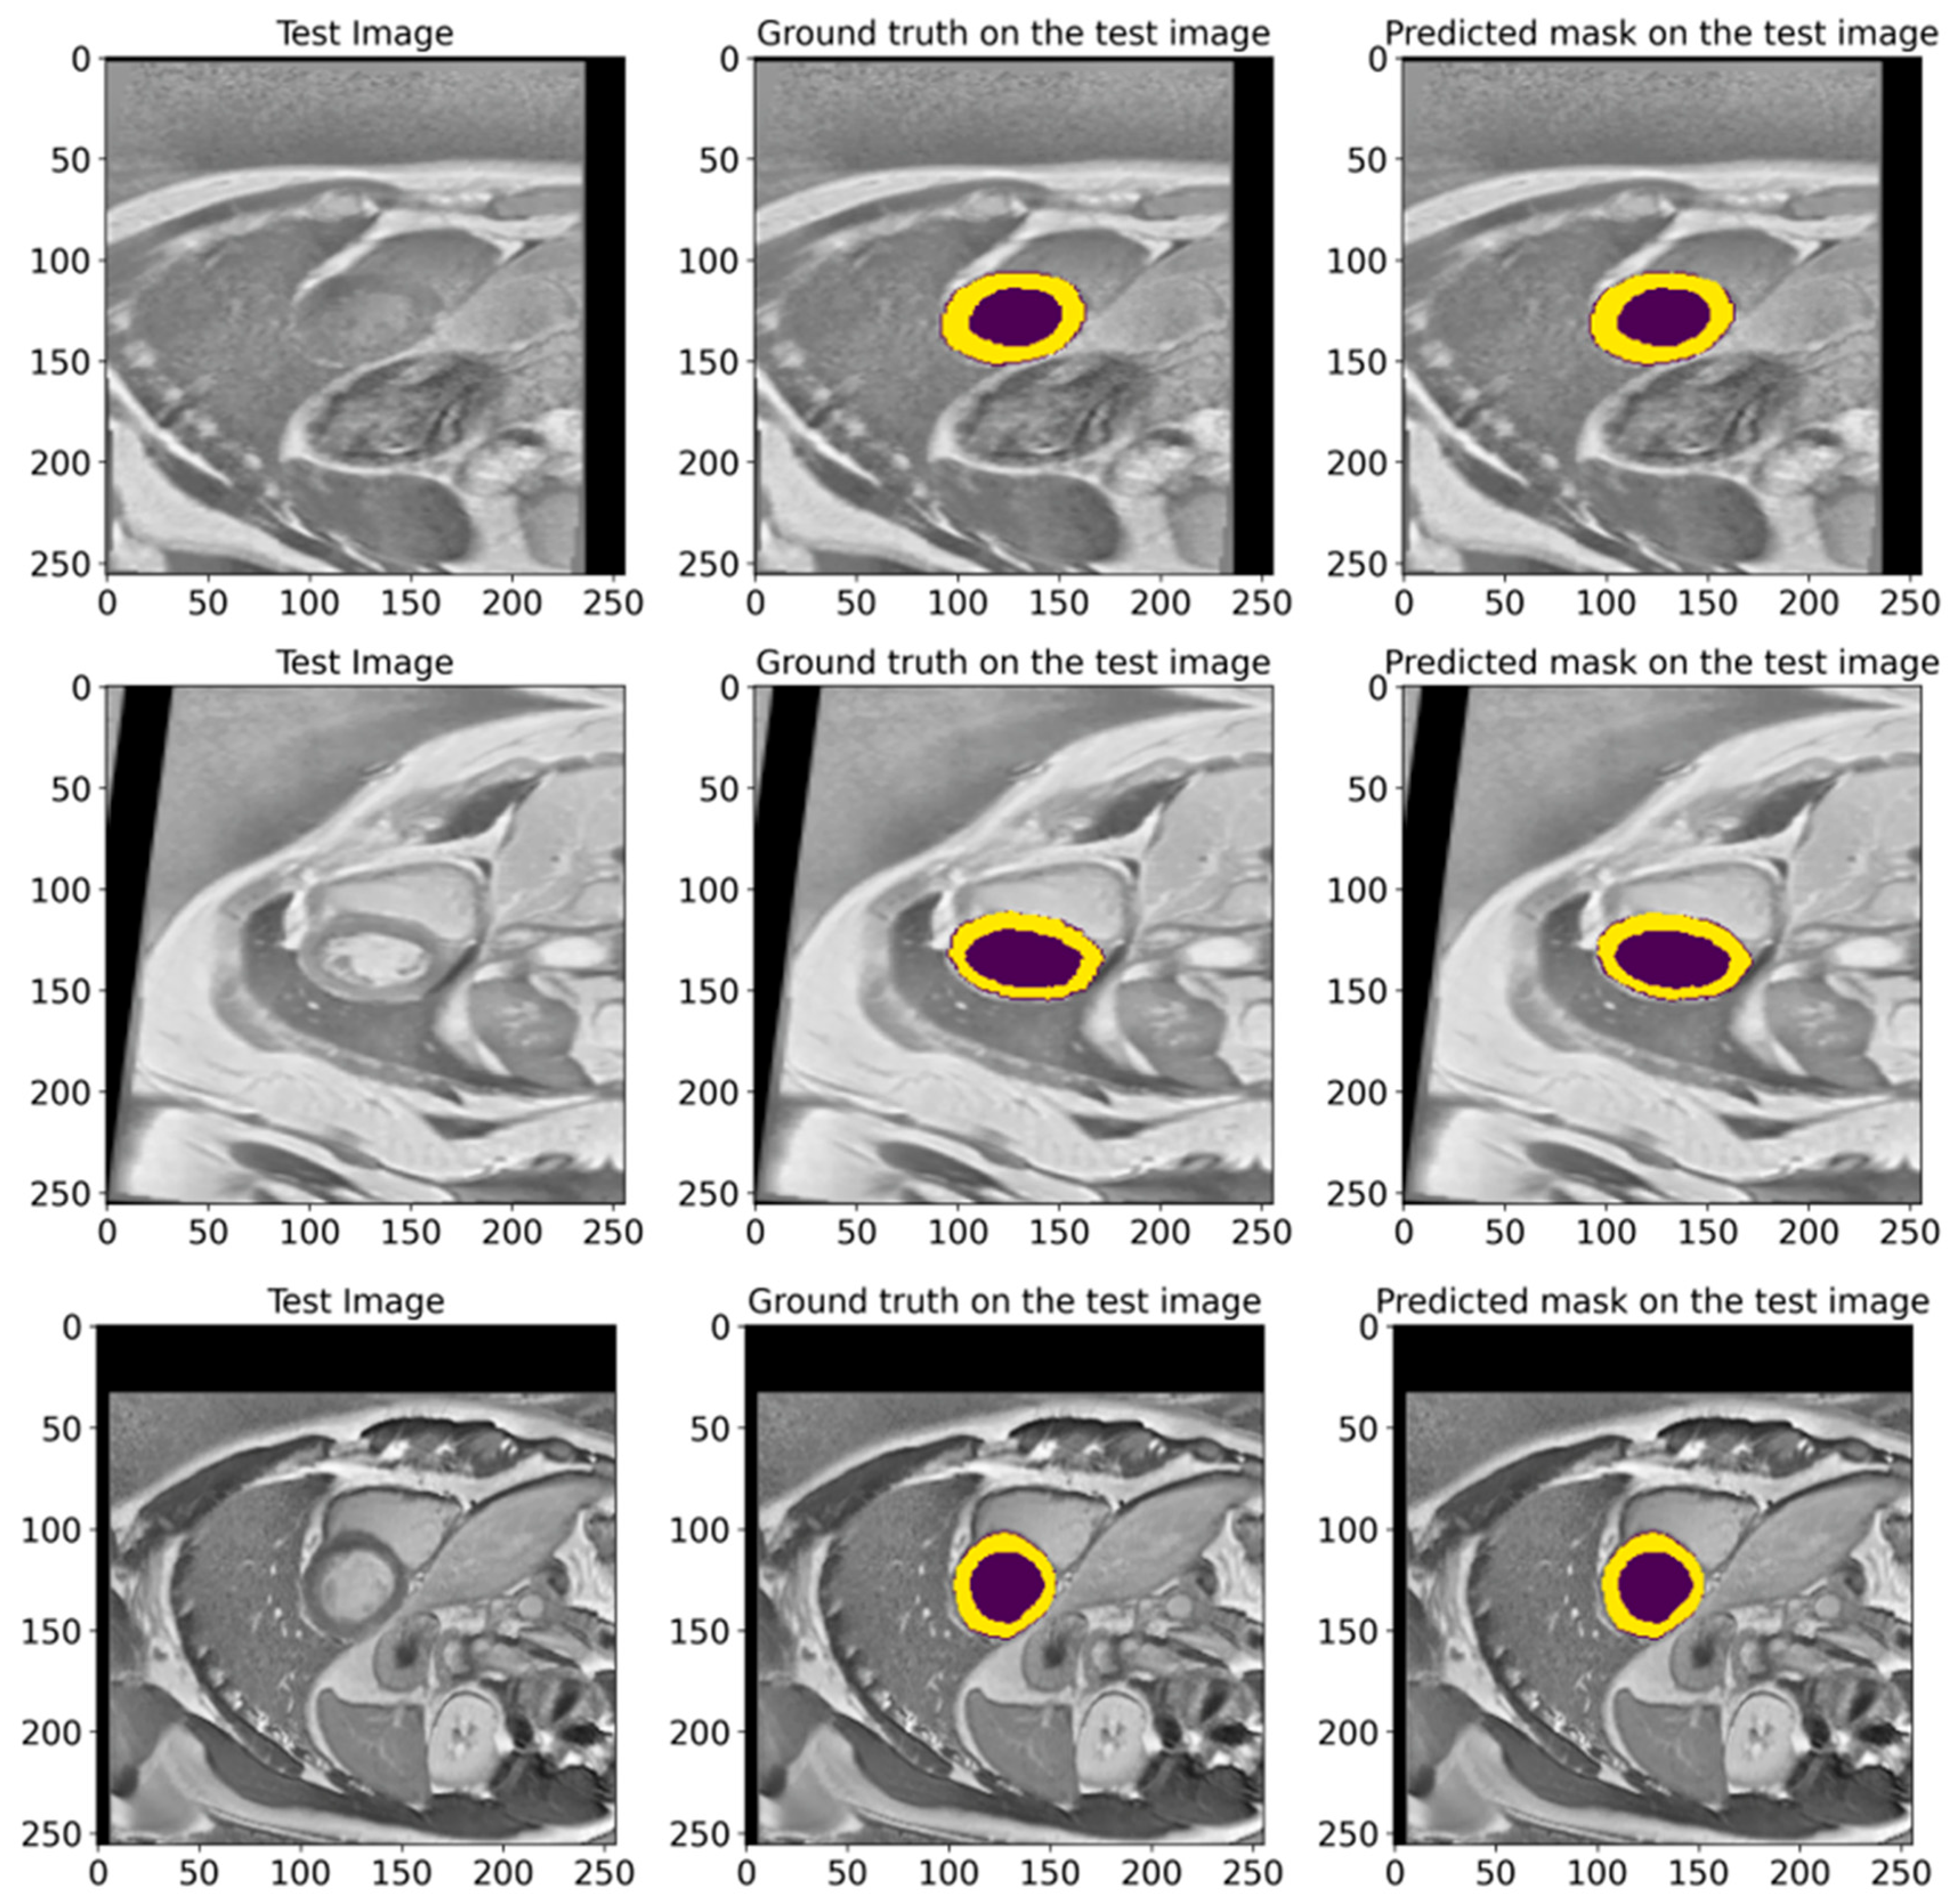

In Figure 16, we show random samples from the test set, along with their GT masks and the predicted masks generated by the model. This visualization illustrates the comparison between the manual annotation conducted with the help of experienced cardiologists and the segmentation outcomes acquired using the developed model. The actual labels represent the true state of the segmented regions and are presented in each image for visual comparison. Looking at the predictions of the model, they indicate how accurately it can reproduce the contours and shapes of the left ventricle and myocardium. The comparison of the images in Figure 16 attests to the high accuracy of the model since the predicted segmentations almost entirely match the actual labels. It further highlights the model’s applicability in clinical settings and its ability to conduct the segmentation task on cardiac MRI images efficiently.

Figure 16.

The visual presentation of random samples of images from the test set from the ACDC 2017 database, with the actual and predicted GT by the model. The visualization shows the comparison between the manual annotation conducted with experienced cardiologists and the segmentation results obtained using the developed model. The deep violet marks the LV regions, whereas yellow outlines the Myo. The high degree of agreement between predictions and actual labels authenticates the precision and reliability of our proposed model in segmenting cardiac MRI images.